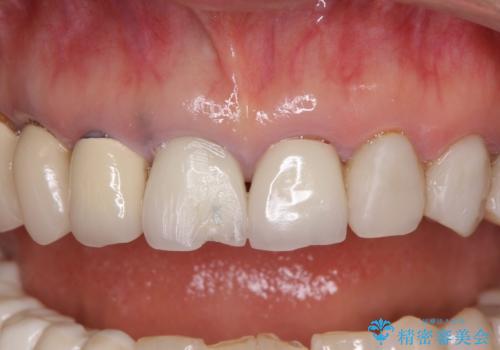

アメリカ国内を転々としながら治療を行ったため治療跡がモザイク様で、クラウンが壊れていたり、抜歯が必要であったりしていました。

下顎右側は骨造成を併用してインプラント治療を行い、その他の奥歯もインプラントや歯周外科処置を併用して補綴治療を進め、最後に前歯部の欠けてしまったセラミッククラウンを作り替えることとしました。